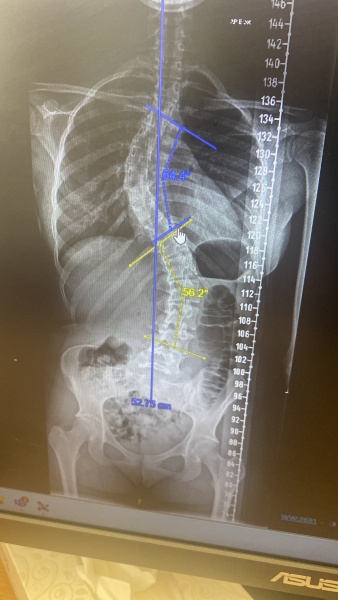

my daughter has just been diagnosed with scoliosis. It’s severe and she needs a big operation. She is just about to submit her UCAS to Sheffield, Nottingham, Exeter and either Newcastle or Bristol. Does anyone have any experience of the pastoral care at these uni’s. She might need to defer at the last minute if recovery doesn’t go as expected. She’s very strongly academically so we would hope she gets offers to at least some of them but we need somewhere where they are on it from a pastoral side.